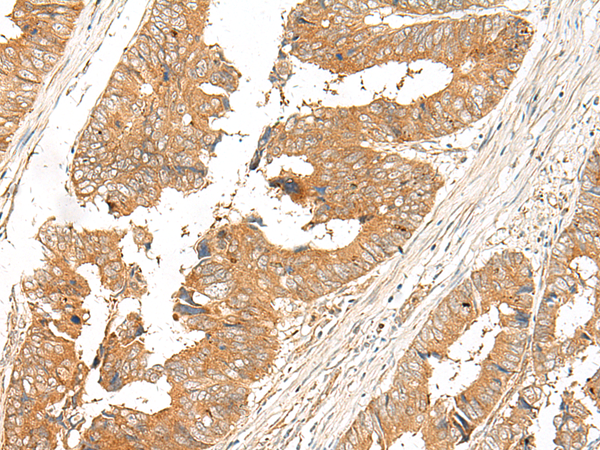

IHC positive control: |

Human cervical cancer and Human colorectal cancer |